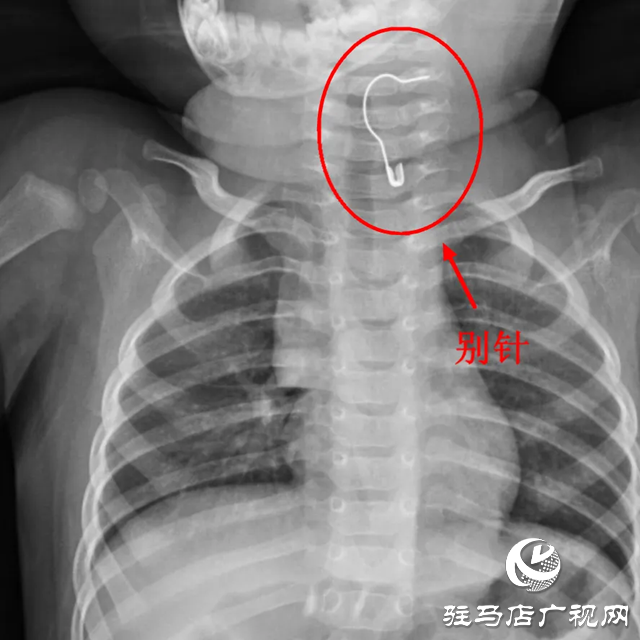

对于家里有小宝宝的家长来说,最头疼的事莫过于宝宝不管抓到什么东西,都喜欢往嘴里塞。十个月大的笑笑,在家玩耍时,不小心吞下一枚别针,家长赶紧送往当地医院,但因异物特殊,笑笑连夜转入驻马店市中心医院妇女儿童医院,儿内二科值班医生史笑敏了解情况后,立即为笑笑安排X线检查,发现金属别针卡在笑笑的颈部食管入口。

别针处于张开状态,尖端外露,危险性不言而喻。史笑敏考虑到别针尖端非常尖锐,若刺穿食管,可能会出现食管穿孔;刺入血管,容易引起大出血;刺伤神经,可能会出现麻木、瘫痪等情况。在与笑笑父母充分沟通后,史笑敏立即联系麻醉医师和内镜中心护士为笑笑进行急诊手术。术中,内镜到达食管处,发现别针张开的尖脚已经扎进了食管

史笑敏在镜下仔细判断,并用异物钳夹住别针裸露的一端,小心地将针尖从食管壁中拔出,所幸的是拔除别针的过程中没有出血,最后顺利地把别针取出体外。几天后,笑笑顺利出院。